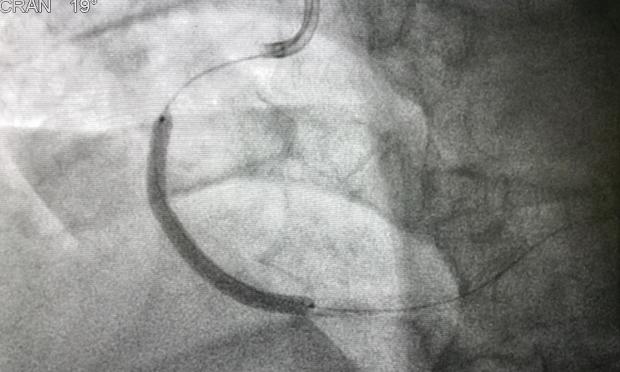

Vol 214, Issue 7: 12 April 2021. Dr Elly Redwood is a Basic Physician Trainee at Prince of Wales Hospital and Community Health Services. Professor David Brieger is an interventional cardiologist and Professor of Cardiology at Concord Repatriation General Hospital. They talk about the importance of ambulance transport to hospital in the event of ST-elevated myocardial infarction, to accompany their research letter at https://www.mja.com.au/journal/2021/214/8/influence-travelling-hospital-ambulance-reperfusion-time-and-outcomes-patients. With MJA news and online editor, Cate Swannell. 12 mins, 31 secs.